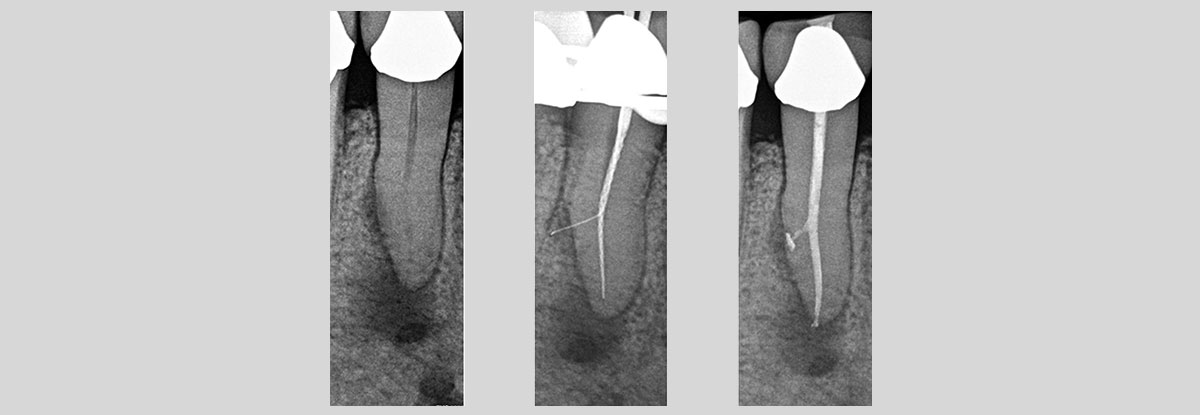

Endodontics / RCT

PROCEDURE :

Step 1

- Local Anesthesia is administered, after which Endodontist removes infection from the canals.

Step 2

- Cleaning and shaping of canals is carried out along with irrigation with sodium hypochlorite.

Step 3

- This protocol is followed till the root apex and ultimately the canal is sealed with gutta percha.